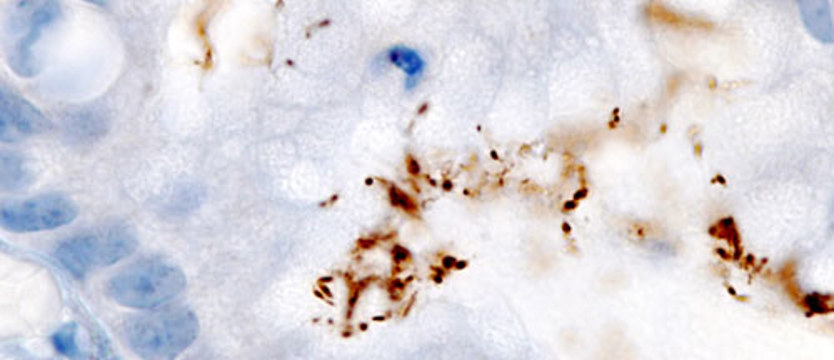

Fot. KGH (commons.wikimedia.org)

Na zdjęciu: Helicobacter pylori wykryty metodą immunochemiczną.